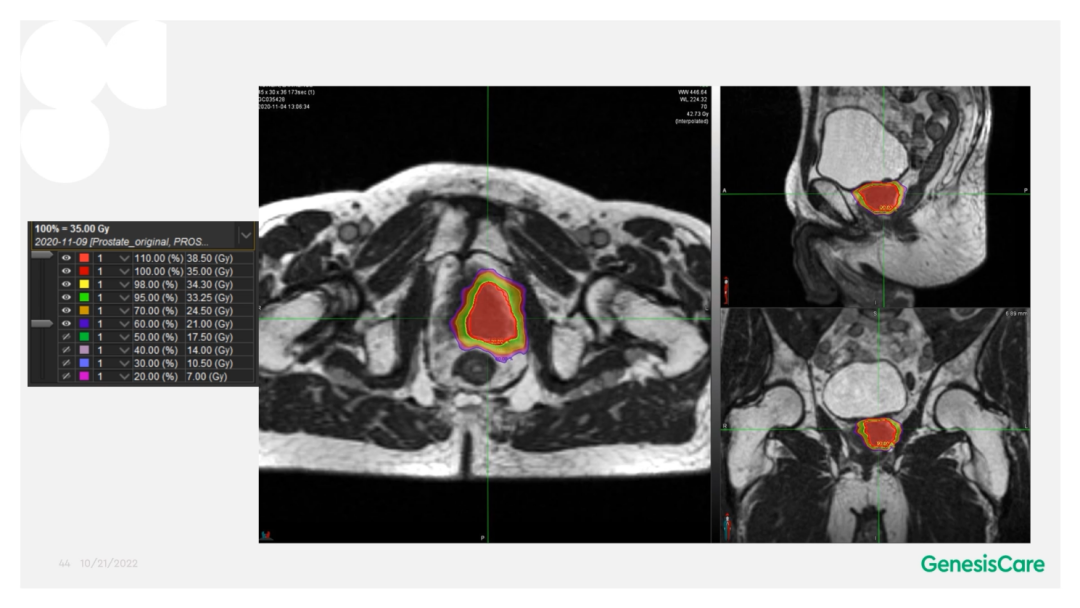

Dr. Camilleri表示,他们在做在线自适应放疗的时候,为了提高速度,仅对靶区外放3cm以内的危及器官的变化进行自适应调整或重新勾画轮廓,见Figure 13。这样可以缩短轮廓勾画的时间。对于放疗计划,使得95%的靶区体积接受到100%的处方剂量覆盖,并将最大剂量限制为2%的靶区体积不超过处方剂量的110%,这样就能保证在图像上很难显示的尿道不会超量,见Figure 14。另外,在制作放疗计划时,将PTV分为PTV LOW和PTV High,PTV和危及器官重叠的部分为PTV LOW,将PTV LOW的剂量目标设定在危及器官的耐受剂量以下,这样就能保证危及器官不超量,见Figure 15。

前列腺癌放疗时若使用原计划的剂量分布,会有较大欠量区,可以通过MRIdian在线自适应优化模块方便地改善欠量。

Figure 16前列腺癌放疗时若使用原计划的剂量分布,有较大欠量区(左);在线优化后的剂量分布,无欠量区(右)